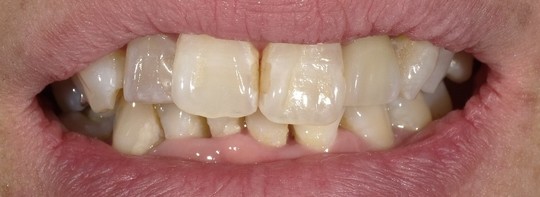

ジルコニアクラウン

BEFORE

年齢:70代女性

治療内容:向かって右上の真ん中から2番目の歯で、保険の修復物の不適合を主訴でいらっしゃいました。

治療期間/通院回数:4回

費用:コア 17,600円

ジルコニアクラウン 194,500円

合計 212,100円 ※2025年7月現在の価格